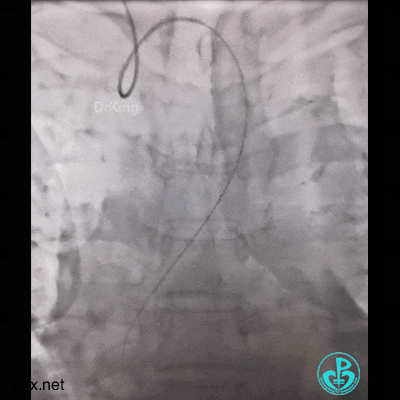

然而:锁骨下迷走,多次尝试TIG根本无法到位。

因为是心梗,患者持续胸痛,生命体征不稳,不再尝试,改腿。

然而,还是不能到位。

带的J-W转,突然血压没了,看下面,悲剧了。

糟糕,打折了,想解开,重新换管子。